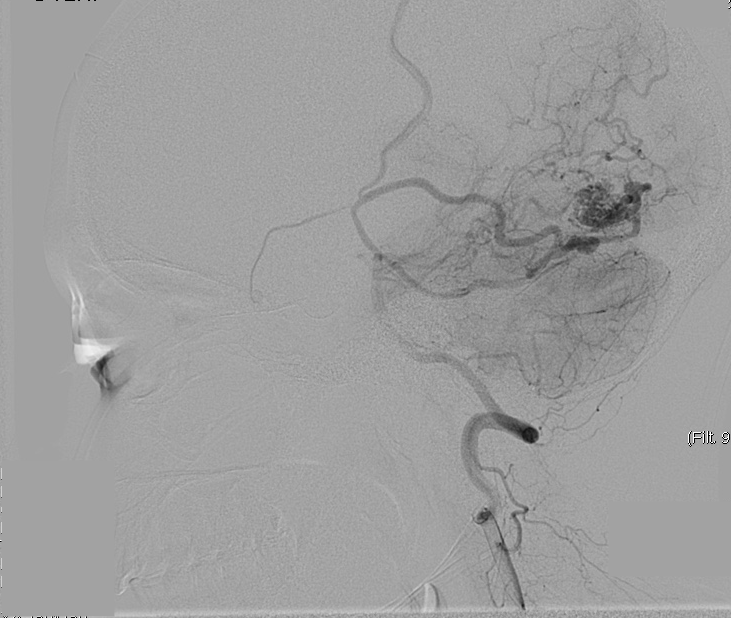

We chose FastICA to define the unmixing function and applied it on 19 DSA image series of subjects with an AVM. The series were composed of 12 to 38 images showing the malformations at different time points and were acquired at a low frame rate of 1.5fps to 6fps. As shown in Figure 2, the function was capable of decomposing the phases of vascular flow. We also generated phase-constrained color-coded overlays for DSA image series through the combination of the recovered sources and vessel masks, leading to a visualization where contrast flow appears progressively and is classified as artery, nidus and capillary, or vein. An example of this visualization is shown in Figure 3.